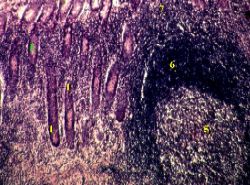

На снимках мы видим участок слизистой оболочки червеобразного отростка.

Лимфоидная ткань.

1. Под криптами находится рыхлая соединительная ткань (3).

2. В ней виден лимфоидный фолликул (4), включающий

светлый реактивный центр (5) из В-иммунобластов и

резко выраженную корону (6) из малых В-лимфоцитов и

3. а) Окружающая область также обильно инфильтрирована лимфоцитами (7).

б) Особенно много их над фолликулом - в поверхностном слое слизистой оболочки, в т.ч. в составе эпителия.